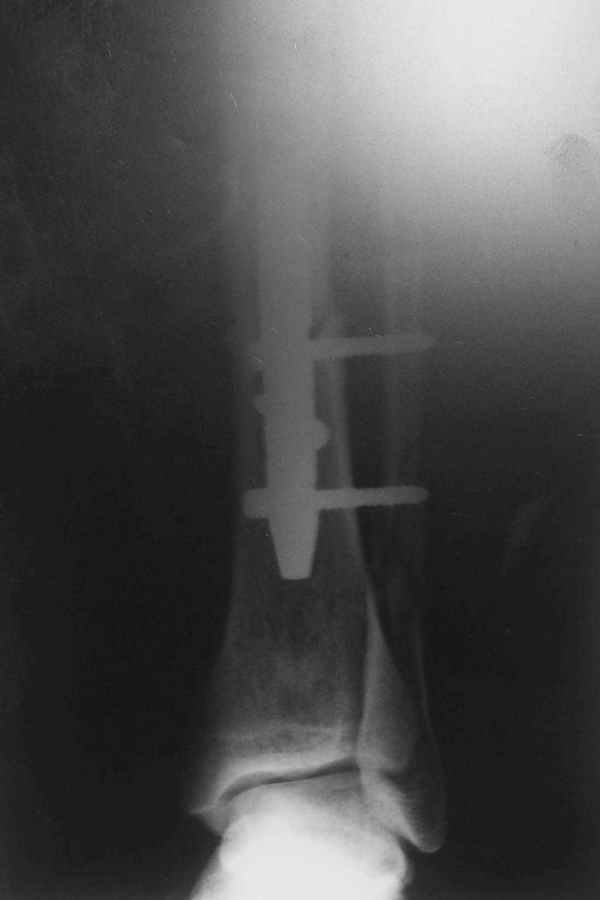

Re: Потекли блокирующие винты, после интрамедулярн

Рентгенограмы